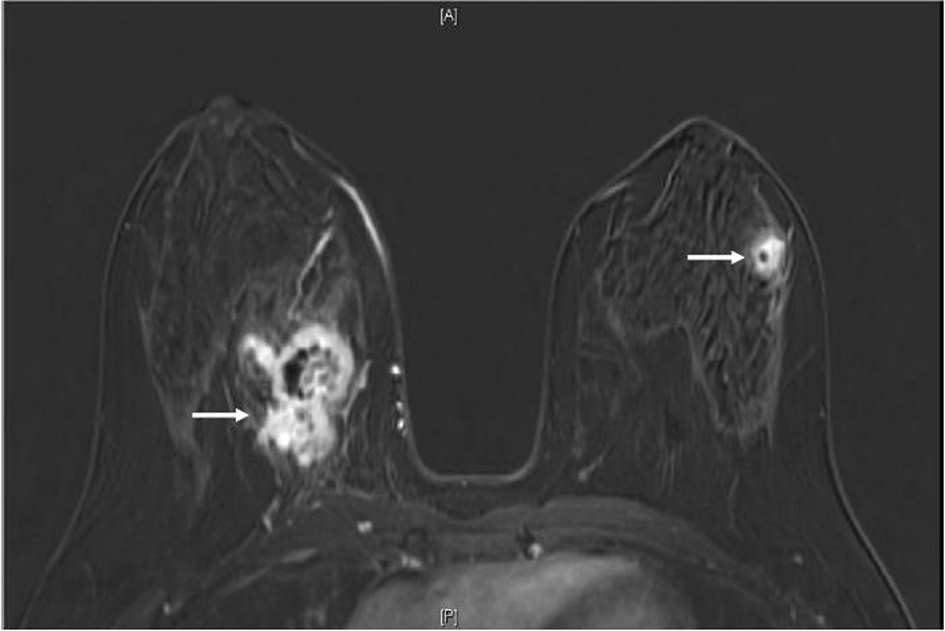

A 34-year-old female with past medical history of sickle cell trait presented to her gynecologist with bilateral palpable breast masses. She was referred for bilateral mammograms and sonograms which revealed a 4.2 × 2.2 × 3.2 cm irregular right breast mass and 1.3 × 1.0 × 0.8 cm left breast mass, highly suspicious for malignancy. She underwent ultrasound-guided core biopsies of both lesions which showed infiltrative, poorly differentiated carcinoma (Fig. 1a). Immunohistochemistry performed for estrogen receptor, progesterone receptor and human epidermal growth factor receptor 2 were negative and Ki67 proliferative index was approximately 70%. At this time, the patient was referred to the oncology clinic. The patient underwent bilateral breast magnetic resonance imaging (MRI) which revealed multiple suspicious enhancing masses in all four quadrants of the right breast, a possible right pleural based enhancing mass and multiple suspicious masses in the left breast (Fig. 2). She was sent for Computed Tomography (CT) of the chest with intravenous contrast to evaluate the pleural mass and was discovered to have multiple pulmonary nodules. A CT-guided fine needle aspiration of a 1.9 × 1.2 cm right lower lobe lung nodule showed malignant cells similar to those from the breast biopsies. Subsequent bone scan revealed multifocal osseous disease involving the thoracic, lumbar spine and right ischium, acetabulum and superior ramus. Options for systemic chemotherapy for the treatment of metastatic triple negative breast carcinoma were discussed at this time.

![]() Click for large image | Figure 2. MRI breast (T1, fat saturated, post-contrast subtraction image) showing the largest right breast mass (left arrow) which is heterogeneously enhancing, with central necrosis and the largest left breast mass (right arrow), also heterogeneously enhancing with central necrosis. |